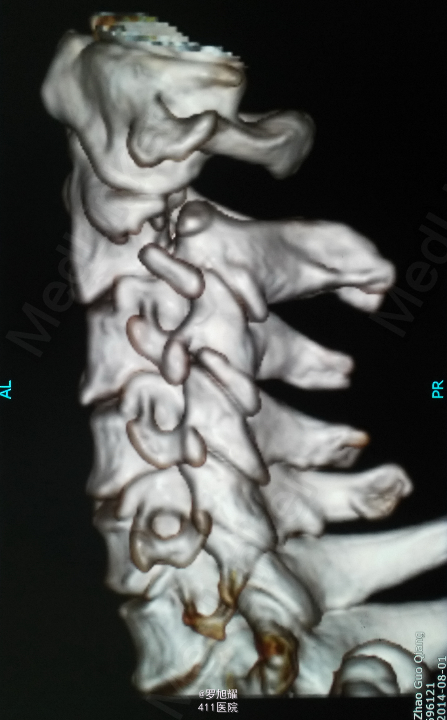

患者男性,64岁。因车祸致颈部疼痛、四肢麻木乏力2小时入院。 该患者同时还有头皮血肿、轻型闭合性颅脑损伤,后期再确诊右肩袖损伤。

左侧锁骨平面以下痛温觉、位置觉消失,右半身感觉正常。会阴部感觉存在。左侧肢体肌力正常,右侧上下肢肌力0级。右侧腱反射均消失。影像学检查示双侧枢椎椎弓骨折,MRI脂肪抑制成像颈1-2平面脊髓信号略高。

入院立即给与大剂量甲强龙冲击治疗,辅以甘露醇脱水消肿,兰索拉唑保护胃黏膜,腺苷钴胺恩经复营养神经,伤后10天复查MRI脊髓信号增高明显,两周后生命体征稳定,肢体感觉和肌力见部分恢复,行颈2椎弓根螺钉、颈3侧块钉内固定术,因神经压迫不明显未行椎板切除减压。 术后3月骨折线基本消失,患者感觉肌力几乎完全正常,右肩残留疼痛磁共振检查发现肩袖损伤,暂予局封治疗症状缓解。